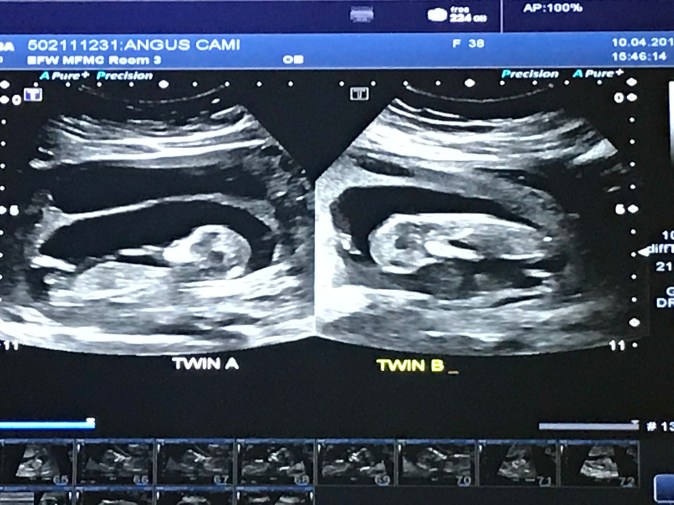

I am excited to say that we are official expecting TWINS and the little bundles of joy will be due October 22nd, 2018. That’s our “due date” but these little guys/girls will likely make an appearance somewhere this September??

Let me tell ya… Twin B likes to party!! He/she is doing what I call “the plank” in this photo. This little nugget WOULD NOT sit still!! It took the ultrasound technician over 20 mins to get a heartbeat because it was moving so much!!

You don’t really feel pregnant (besides the nausea, the bloating, the peeing 3 times a night, the INSANE exhaustion, the weird food aversions, did I mention nausea…??) till you see them moving. It really didn’t feel real to me till I saw them moving on Tuesday and Wednesday. Their tiny little hands and toes (they kinda look like skelator in the scans) and its neat to see their little hearts beats fluttering.